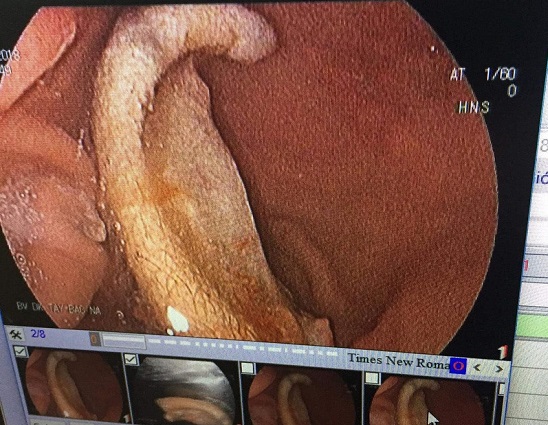

Còn bệnh nhân Đ., các bác sĩ đã dùng máy móc, thiết bị y tế kiểm tra phát hiện chiếc tai trong bụng chưa bị nhai nhỏ, vì vậy đã tiến hành nội soi gắp thành công chiếc tai ra ngoài.

Liên quan đến vụ việc, thông tin từ khoa Tai Mũi Họng, bệnh viện Hữu nghị Đa khoa Nghệ An cho hay, miếng tai gắp từ bụng V.M.Đ đã quá 6 tiếng (thời gian có thể nối liền sau khi đứt rời) và đã bị nhiễm khuẩn bởi các dịch của dạ dày nên việc ghép nối đã không thể thực hiện được.

Do phần tai bị nuốt vào bụng đã bị nhiễm khuẩn nên không thể nối lại. Ảnh: Người Đưa Tin |

Sau đó các y, bác sỹ đã tiến hành tái tạo lại vành tai cho T. bằng kỹ thuật tạo vạt. Hiện sức khỏe của bệnh nhân đã ổn định và đang hồi phục.